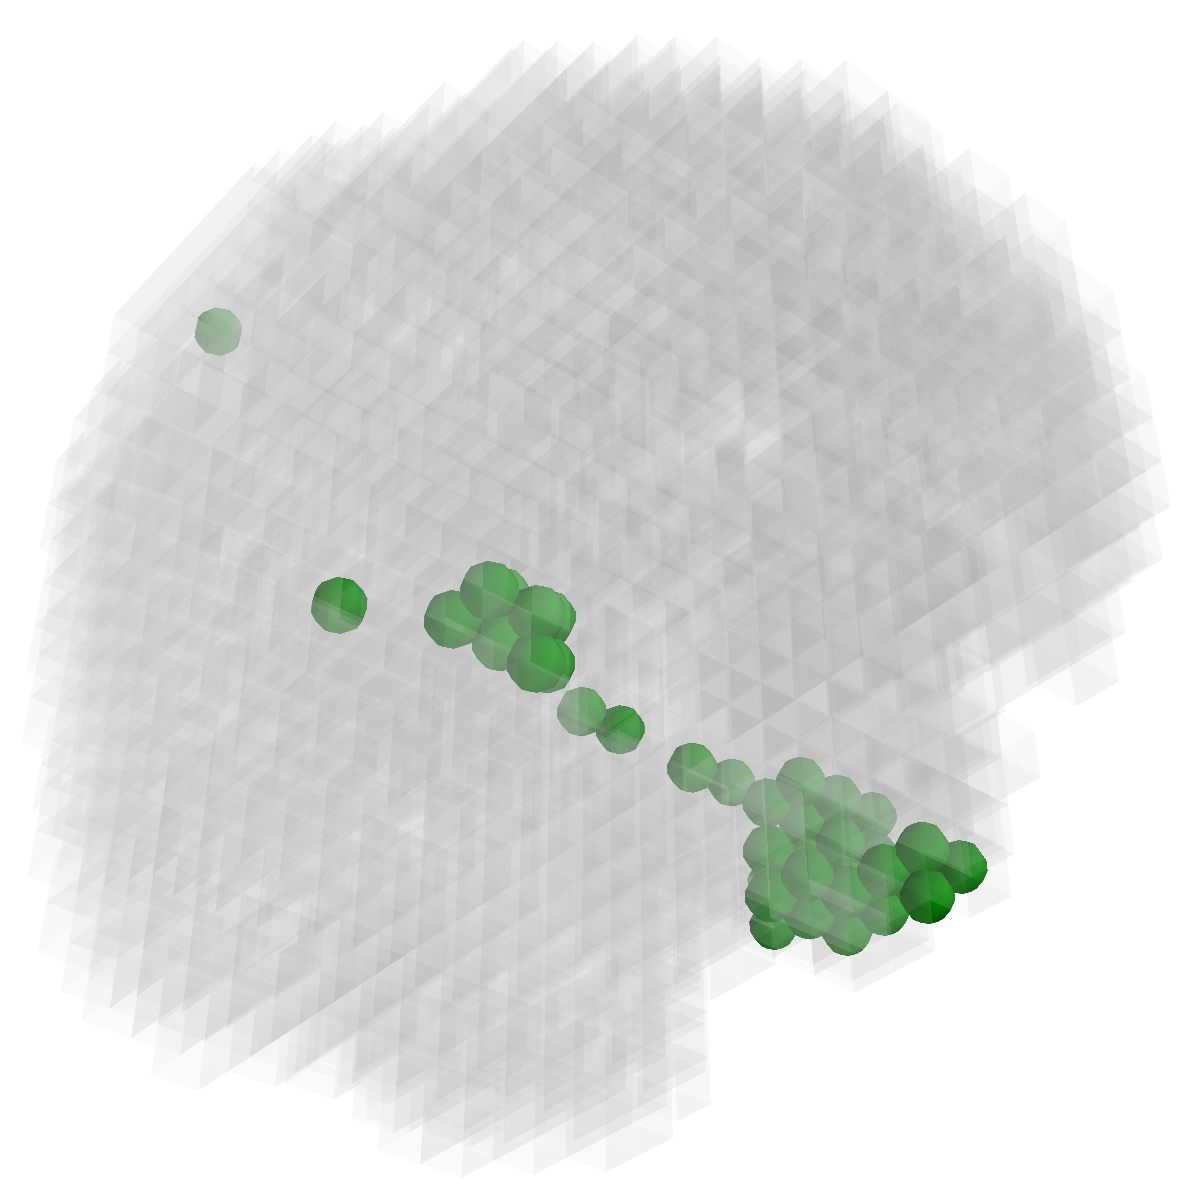

Figure 2: Feature selection by different models. The top row illustrates selected voxels in a 3D model (voxels with positive β𝛽\beta are in brown and negative ones are in blue), the mid and bottom rows illustrate the corresponding projections on brain slices.

Feature selection. For each task, the selected features are those whose β𝛽\beta are not zero . In Figure 2, the result of 30ADNC is used to illustrate the feature selection by different models (using the parameters at their best accuracy). As shown, the selected voxels by both GFL and n2superscript𝑛2n^{2}GFL cluster into several spatially connected regions, whereas those of lasso and T-test/MLDA scatter around. Also, as mentioned before, the LapL tends to select much more voxels than necessary due to the l2subscript𝑙2l_{2} regularization. Moreover, the selected voxels by GFL and n2superscript𝑛2n^{2}GFL are concentrated in Hippocampus, ParaHippocampal gyrus (which are believed to be the early damaged regions). On the other hand, the lasso and T-test/MLDA either select less lesion voxels or select probably noisy voxels not in the early damaged regions.